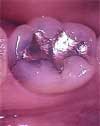

Many people have silver/mercury fillings from years past in their mouths. These fillings are not particularly pleasing to the eye, and we know that by unavoidable design, silver/mercury fillings ultimately result in a weaker tooth structure. Porcelain inlays and composite resins create fillings that are not only beautiful (or invisible) but also add strength to weakened teeth. These restorations are esthetically pleasing and very strong thanks to new bonding technologies.